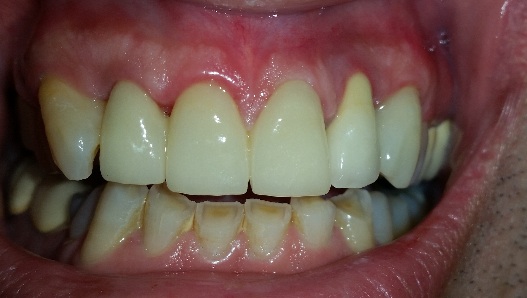

Il paziente si presenta in studio con un sorriso oggettivamente insoddisfacente. Dopo documentazione fotografica del caso si procede con lo studio dell'estetica adottando il principio del Digital Smile Design accompagnato da un attento esame clinico parodontale e radiologico. Si propone al paziente in intervento di riposizionamento gengivale e osseo seguito dal confezionamento di un provvisorio su elementi 11 12 21 e 23. Purtroppo l'elemento 22 è una corona su impianto "intoccabile". Successivamente si esegue una riabilitazione protesica di massimo livello estetico con zirconio-ceramica.